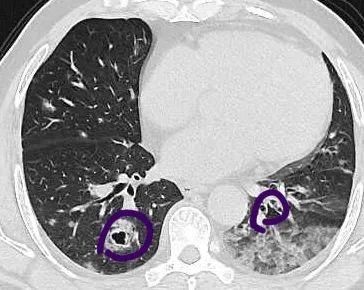

2020年5月左右,一向身体很好的张伯却无缘无故出现了咳血症状,当地医院肺部CT检查结果显示,他双肺布满了圈状的病灶,看过去就像是一个个白色的圆圈,大小不一,最大的有手镯那么大,共计有七八个。

文章插图

紫色圈里均为病灶

这奇怪的表现让当地医生犯了愁,进一步气管镜检查后,并未发现肿瘤细胞,于是诊断为肺炎,给张伯开了抗生素消炎药,并要求他每3个月复查。

张伯吃了3个月的药,感觉咳血情况好了一些,但复查结果显示他肺部的“圈圈”更大,数量也变多了。治疗无效?

那是什么原因,让张伯肺部腺癌呈现“圈状”,并且穿刺都未发现肿瘤细胞?

“这是非常少见的肺炎样肺癌,一般来说,肿瘤病灶都是实心,就算形态不一,都较容易判断。但这位患者的腺癌肿瘤细胞有分泌粘液的功能,分泌出的粘液将肿瘤包裹起来了,就在影像学上呈现出圈状。一般这种分泌型肿瘤常见于消化道,肺部非常少见,很多医师可能都没遇到过,容易错认为肺炎。”医生说。

同时,由于分泌型肿瘤周围一大圈都是粘液,穿刺如果不够深入的话,相当于就只取到了外围的粘液,没有取到肿瘤组织本身,使得病理报告不准确,也容易造成误诊。